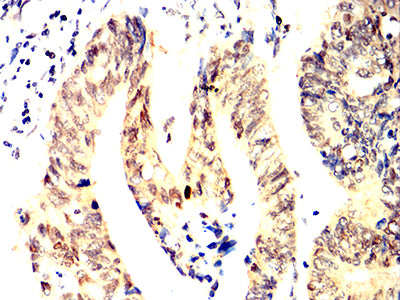

- Immunohistochemical analysis of paraffin-embedded human rectum cancer tissues using ACHE mouse mAb with DAB staining.